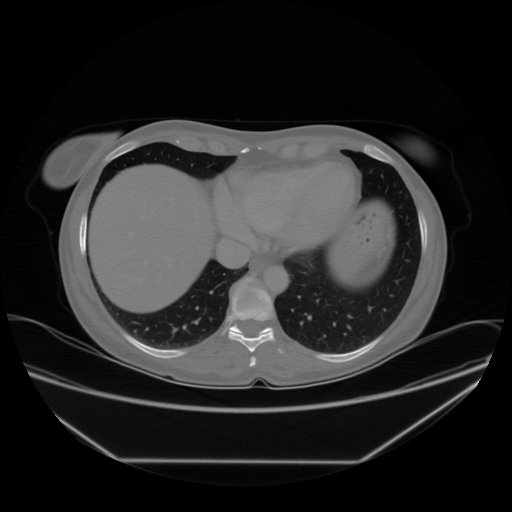

Image Grid

4Γ—3 grid: Rows show different image types (Original NATIVE, Reconstructed NATIVE, Original VENOUS, Generated VENOUS), Columns show windowing techniques (No Window, Lung Window, Mediastinum Window)

Original NATIVE CT scan (input)

Full window (WL 1023.5, WW 4095 β†’ Low βˆ’1024, High +3071)

Generated VENOUS CT scan (A→B translation)